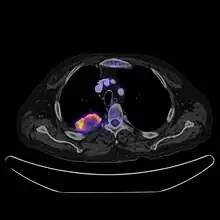

PET CT

Positron emission tomography–computed tomography is a hybrid CT modality which combines, in a single gantry, a positron emission tomography (PET) scanner and an X-ray computed tomography (CT) scanner, to acquire sequential images from both devices in the same session, which are combined into a single superposed (co-registered) image. Thus, functional imaging obtained by PET, which depicts the spatial distribution of metabolic or biochemical activity in the body can be more precisely aligned or correlated with anatomic imaging obtained by CT scanning.[24]

PET-CT gives both anatomical and functional details of an organ under examination and is helpful in detecting different type of cancers.[25][26]